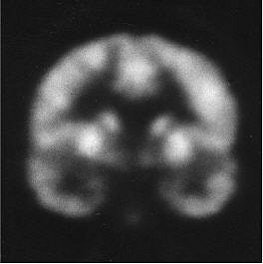

| Above, regions of interest (ROI) examined in MRI study of patients with first-episode schizophrenia or affective psychosis and normal comparison subjects. Top (A) is a 1.5-mm coronal slice of the temporal lobe; the ROI used to evaluate the temporal structures are outlines. The gray matter of the superior temporal gyrus is shown in red (subject left) and green (subject right); more medially, the amygdala-hippocampal complex is shown in orange (left) and blue (right) with the parahippocampal gyrus underneath in pink (left) and purple (right). Below, a left lateral view of a 3D reconstruction of the cortical surface with the anterior superior temporal gyrus (light pink) and posterior superior temporal gyrus (red). |

![]() |

| Same subject. Above and below, axial MRI is used to present top-down views of the 3D reconstruction of the amygdala-hippocampal complex and parahippocampal gyrus. All images: Figure 1, Hirayasu Y, Shenton ME, Salisbury DF, et al. "Lower Left Temporal Lobe MRI Volumes in Patients with First-Episode Schizophrenia Compared with Psychotic Patients With First-Episode Affective Disorder and Normal Subjects," (Am J Psychiatry 1998; 155:1384-1391). |